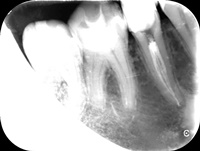

Pacjentka zgłosiła się z bólem. Kilka miesięcy wcześniej leczona kanałowo lewa dolna szóstka. Ząb wrażliwy na nagryzanie. Podjęto decyzję o ponownym przeleczeniu kanałów korzeniowych. Zamknięto perforację przy wejściu do dalszego kanału, usunięto złamaną igłę lentulo z dalszego kanału, udrożniono mezjalne kanały, aż do perforacji korzenia w policzkowym bliższym kanale. Wypełniono dalszy kanał gutaperką, bliższe kanały wypełniono MTA. Ząb do obserwacji, najprawdopodobniej będzie wykonana resekcja wierzchołków bliższego korzenia, na poziomie perforacji.

Reendo 46.